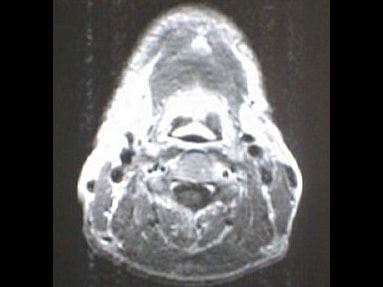

中咽頭末期がんMRI画像①

入院当時MRI画像①

中咽頭末期がん消滅時MRI画像①

入院3か月後癌消滅MRI画像①